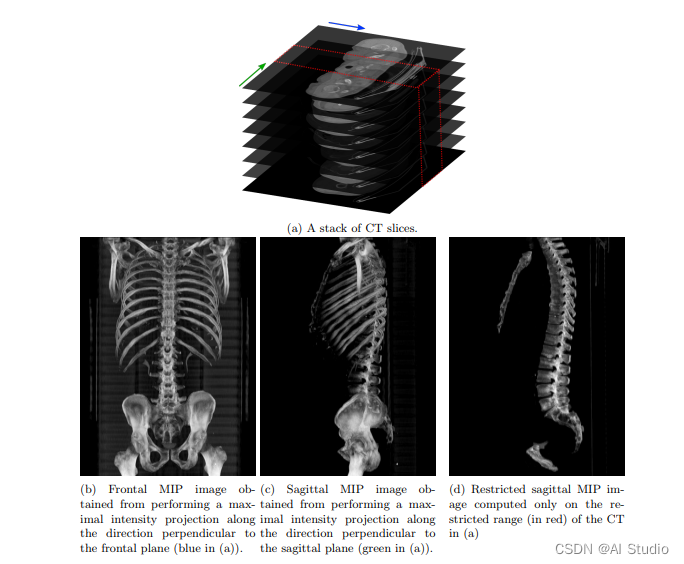

首先,通过最大强度投影(MIP)将三维CT图像转换为二维图像,从而降低了问题的维数。

本项目将3D CT体积作为输入。体积通过最大强度投影(MIP)转换为2D图像,并进行进一步后处理。

所有1070个3D CT图像都经过预处理,其中每个3D图像都会生成一组由正面图像和受限矢状图像组成的图像。